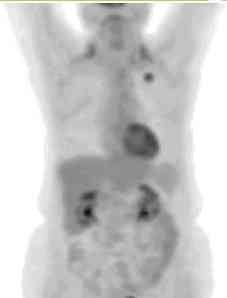

pet_breast1.jpg (3492 bytes) Left breast cancer

The FDG PET exam on the left  is from a 53 year old female patient being evaluated for a right upper lobe pulmonary nodule detected on CT scan. The pulmonary lesion demonstrates no abnormal FDG accumulation strongly suggestive of a benign lesion. An unanticipated finding was focal FDG accumulation in the upper left breast which proved to be due to an infiltrating ductal carcinoma. Note the symmetric uptake in the posterior lower cervical muscles which can be seen in tense patients. Some laryngeal tracer accumulation is also seen and can be attributed to talking. Other areas of physiologic tracer accumulation can be seen in the myocardium, kidneys and collecting systems, urinary bladder, gastrointestinal tract, liver, spleen, and marrow.